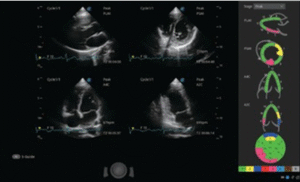

• Cardiology

Echocardiography remains one of the gold standards for diagnosing and monitoring heart disease, including cardiomyopathies, valvular disease, and pericardial effusion.